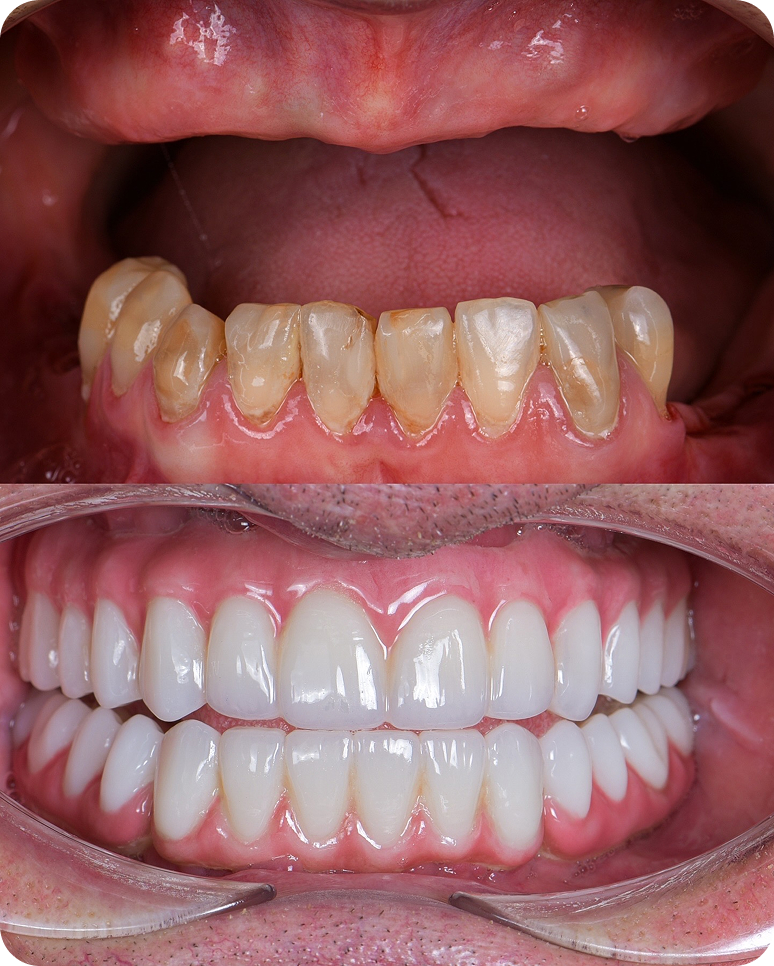

Улыбка до/после

Несъемные протезы